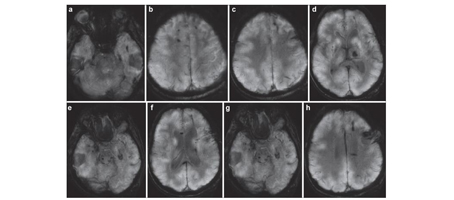

9. Neurocutaneous melanosis with intraspinal malignant melanoma in adults-an extremely rare clinical entity: A case report with review of literature

Dongkang Liu, Yujun Wei, James Wang, Guihuai Wang

临床转化神经科学    2016, 2 (4): 236-240.   DOI: 10.18679/CN11-6030/R.2016.039

摘要459)      PDF (3124KB)(487)

Objective: Neurocutaneous melanosis (NCM) in adult patients was rare, and few cases had been reported. In this report, we summarized the features of NCM in adult patients for providing useful information about this rare clinical entity.

Methods: In this report, we present a case of a 41-year-old woman, who was eventually diagnosed with NCM with intraspinal malignant melanoma. The clinical features, treatments, and prognosis of cases of NCM in adults were thoroughly reviewed and discussed.

Results: A 41-year-old woman was eventually diagnosed with NCM with intraspinal malignant melanoma. The post-operative course was uneventful and her symptoms significantly improved (VAS: 3 points). However, she developed symptoms of intracranial hypertension and deteriorated rapidly after 11 months of operation, and died 1 month later. To date, only 15 cases of NCM in adults have been reported in the English literature. Analyses showed that the average age was 33.8 years (range 19-65 years), and 11 patients (68.8%) were between 20 and 40 years. A slight male predominance (M:F/11:5) was found. For the 12 cases which detailed follow-up information was available, 9 patients (75%) died, with a survival time ranging from 1 day to 29 months post-operation. Death occurred within the first month of operation in 6 cases (46.2%). The median survival time was 3 months.

Conclusions: We presented a rare case of NCM with intraspinal malignant melanoma in an adult patient. Although rare, this clinical entity causes significant mortality and has poor prognosis.

图表 | 参考文献 | 相关文章 | 多维度评价